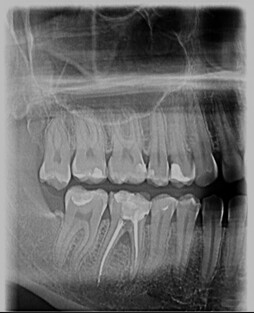

Dexis OP 3D Pro donosi potpuno digitalno rešenje za ortopantomogram (OPG), telediogram, skanogram, bitewing, i 3D snimke vilice, čime pruža sveobuhvatnu podršku dijagnostici za različite stomatološke zahvate i analize.

Bilo da vam je potrebno jednostavno snimanje zuba ili složeniji pregled maksilarnih sinusa i TM zglobova, naš centar je tu za vas.